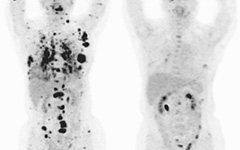

乳がんから骨へ―【多発性骨転移、根治を希望】乳がんを全摘出して5年、骨転移を確認。根治を希望したため抗がん剤ではなく免疫治療を希望、複数の治療法の組み合わせにより1年でほぼ消失。